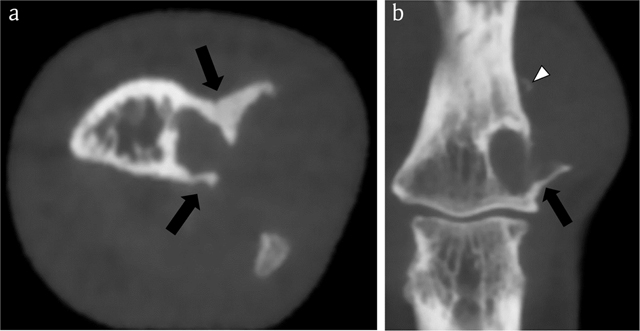

Figure 8

Case 2 – CBCT. Axial image (a). Coronal reformatted image (b). The lesion consists of a smaller intramedullary and a larger juxta-cortical component. The intramedullary part is well-delineated by a rim of peripheral sclerosis, whereas the juxta-cortical part causes scalloping of the outer cortex within overhanging edges (black arrows in a and b). The cortical breakthrough and overhanging margins are far better demonstrated than on CR (see Figure 6). Note a small fleck of calcification (white arrowhead), supporting the hypothesis that the lesion contains chondroid matrix.